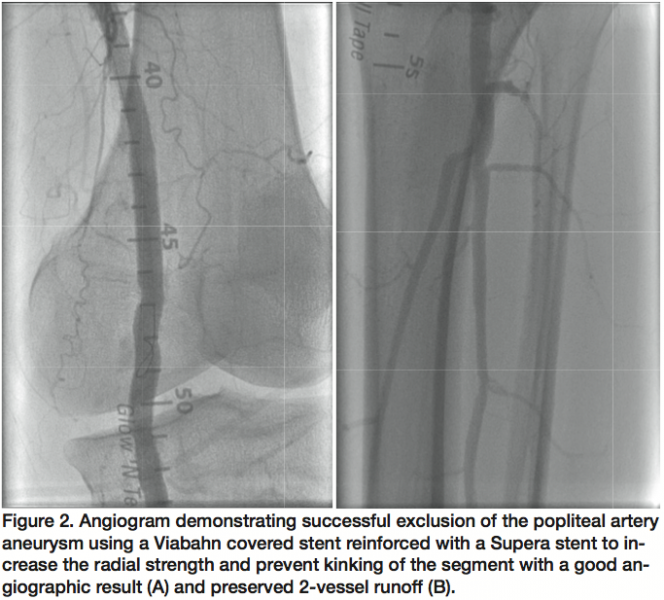

A 64-year-old man was admitted for peripheral angiogram due to symptoms of bilateral lower extremity lifestyle-limiting claudication. Selective angiogram of the left lower extremity showed a heavily calcified mid to distal SFA with 80% diffuse, ulcerated stenoses, and a 2 cm PAA with 3-vessel runoff (Figure 1). Percutaneous intervention of the SFA was performed with Turbohawk directional atherectomy (ev3 Endovascular, Inc.) in the SFA followed by balloon angioplasty with good angiographic result. The PAA was then successfully excluded by deployment of a 7 x 150 mm Viabahn stent (Gore Medical), which was postdilated with a Sterling 7 x 100 mm balloon (Boston Scientific). A Supera 6 x 120 mm, self-expanding, high radial strength stent (IDEV Technologies Inc.) was then deployed within the Viabahn stent (Gore), covering the distal and proximal landing zones in order to reinforce the covered stent. There was a good angiographic result with brisk flow and preserved 3-vessel runoff (Figure 2). The patient was discharged home the following morning and had no complications in 3 months of follow-up.